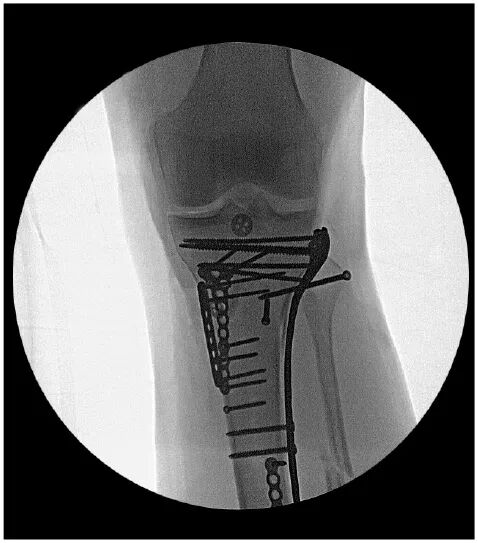

Intraoperative fluoroscopy radiographs showed near anatomic restoration of the bony anatomy (Fig. 4). Multiple minifragment plates and independent lag screws were used for fragment-specific fixation and provisional reduction control. The proximal tibial locking plate was used after fragment-specific fixation in neutralization mode for definitive fixation. The bony PCL avulsion fragment, including the insertion of the posterior horn of the lateral meniscus, was repaired using proximal and distal button fixation bridged with SutureTape. This was accomplished via the posteromedial approach utilized for bony fixation that was extended intracapsularly. An iatrogenic ramp lesion (meniscocapsular separation) was created to improve exposure, and this was repaired primarily upon closure. The fibula was reduced and secured with a screw.

Figure 4: Intraoperative AP fluoroscopic radiograph shows near anatomic reduction.